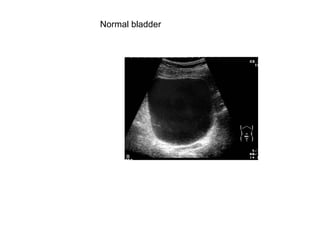

The normal bladder

Normal bladder